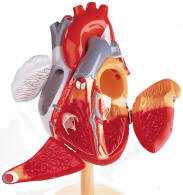

| Human Body Circulatory System -

bulk of the pages are on the Human Heart. The Starter Hearts vary

to more advanced models. The pages that follow portray

increasingly detailed models, including many suitable for advanced

medical school education. These are suitable for internal medicine

and the study of cardiovascular diseases.